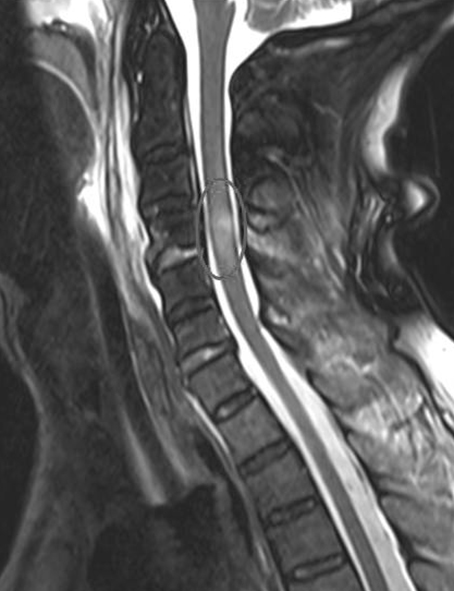

El nivel de lesión cervical fue C4 en el 50% de los casos, C5 en un 37% y C6 en el 13% de los casos. La lesión medular al ingreso fue clasificada en un 75% (6 casos) como ASIA A, 25% (1 caso) ASIA B y un 25% (1 caso) ASIA C. Los dos casos incompletos presentaban un síndrome centromedular de Schneider (Tabla 1).

Luxación |

Si |

A |

Completa |

Doble abordaje |

Hemos estudiado (deportistas veteranos que ha sufrido una lesión medular cervical tras una caída en bicicleta durante la práctica del ciclismo y se ha evaluado su evolución neurológica. Se ha constatado la posibilidad de mejoría neurológica en aproximadamente un 40% de los pacientes. Los resultados obtenidos en el estudio establecen que tras la caída en bicicleta hasta un 11% de las ocasiones se asocia una lesión medular cervical con una tetraplejia concomitante secundario al mecanismo de hiperextensión cervical. En diversas series evaluadas (5), la incidencia de lesión medular cervical oscila en torno al 4%, no obstante, la actividad deportiva ecuestre sigue siendo la actividad que mayor número de lesionados medulares genera, rondando un 42% de los casos (6)(7).

La alta prevalencia de lesionado medular tras caída en bicicleta demuestra que es un problema de primer orden y con una repercusión funcional devastadora cuando no se realiza un tratamiento adecuado. Sin embargo, el 25% de los pacientes atendidos en nuestro centro evolucionaron favorablemente de una lesión medular completa (ASIA A) a una lesión medular incompleta con posibilidad de deambular de forma autónoma (ASIA C). A tenor de los resultados obtenidos destacamos que el paciente afecto de lesión medular incompleta pueda mejorar hasta en un 25% de los casos un nivel neurológico. De la revisión bibliográfica realizada en relación con el déficit neurológico al ingreso, nuestra serie difiere con otras publicaciones. Boran et al., (8) aportan una incidencia de un 60% de lesión cervical tras caídas sobre región cervical con la práctica deportiva, presentando un 36% de los pacientes un déficit neurológico; 35% lesionado medular completo y un 65% incompleto). Por su parte, Roberts et al. (9) constatan un mayor traumatismo espinal cervical con caídas en bicicleta de montaña respecto a la bicicleta de carretera que es debido al mecanismo de hiperextensión cervical al descender una pendiente y golpearse en el suelo practicando bicicleta de montaña.